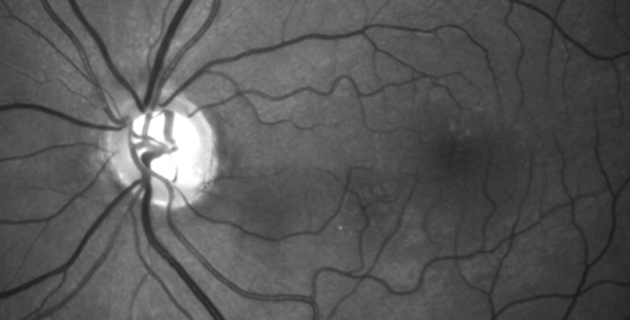

Da die Dicke der Hornhaut Einfluss auf die Augeninnendruckwerte hat, erfolgt zunehmend die Hornhautdickenmessung (Pachymetrie) zur kritischen Überprüfung der Werte. Hohen differenzialdiagnostischen Stellenwert haben auch die Beurteilung des Kammerwinkels (Gonioskopie) und des Sehnervenkopfes. Mittels optischer Cohärenztomographie (OCT) ist eine Quantifizierung des Verlustes an neuroretinalem Gewebe möglich. Die fotografische Dokumentation von Papille und Nervenfaserschicht erleichtert die Verlaufsbeurteilung. Die Gesichtsfelduntersuchung (Perimetrie) ist ein entscheidender Teil der Diagnostik.